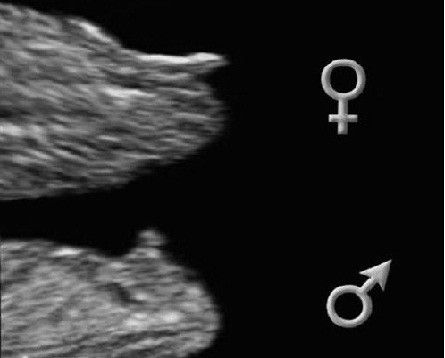

Всё о нашей беременностиДождалась наконец-то первого скрининга. Ну что сказать, неожиданности случаются! 😁 Изначально не хотела знать пол, думала про гендер пати и всё такое, но, наш малышонок решил по другому. Как только я сказала доктору, мол если будет какой-то намёк на пол - не говорите, поднимаю глаза на монитор, а там прелести во всей красе, захочешь развидеть - не получится 😝 Так что вот так вот, в 12 недель бывает, что уже безошибочно всё видно, для тех, кто сомневался, что можно 100% узнать пол на таком сроке)

У подруги тоже в 12 недель мальчик был на УЗИ, а в 16 - девочка) родилась девочка) "Причиндалы" формируются ближе к 15 неделям, до этого срока половые органы и мальчиков, и девочек выглядят примерно одинаково, пипка такая (половой бугорок), отличается углом наклона только.

Alice, в это сложно поверить, но да, у девочек на этом сроке тоже торчит, только более горизонтально. У мальчиков торчит под углом. На таком сроке лучше не настраиваться пока на конкретный пол, велика вероятность ошибки. Если вам нужно знать точно и в ближайшее время, лучше сдайте анализ крови на определение пола. А на УЗИ пол имеет смысл смотреть в 15-16 недель.

В 12 недель у девочек половой бугорок такой же на вид, как и у мальчиков, отличается только угол наклона, по нему и делают предположительные прогнозы узисты)

Сильно не надейтесь, на вашем сроке ещё нет половых органов, бугорок и у девочек такой же точь в точь)